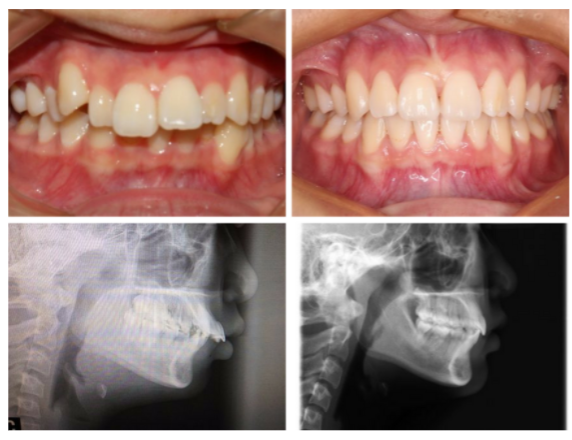

全头xray我们可以看到牙齿矫正前后侧面脸型和嘴型产生的变化。当然,由于她的过咬合非常严重(上下排差距太大),拔去了上牙的左右两颗第一前臼齿,能够把整个上排往后退并调整下排牙齿角度,使牙齿能够达到标准咬合。

这个是我们常说的龅牙(天包地),除了上排牙突出之外其他牙齿也很整齐没毛病。这个妹妹也是拔掉了左右两颗第一前臼齿,把整排上牙往后推,总共是35个牙套,时长10个月。